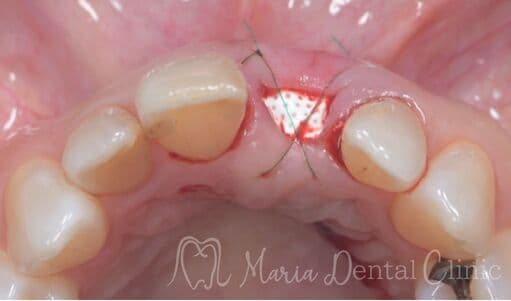

結合組織移植術(CTG)により機能および見た目を改善

抜歯後に生じた歯肉の陥凹は、見た目の不調和や清掃性の低下を招くことがあります。本症例では、ブリッジ治療に先立ち、結合組織移植術(CTG)を行い、失われた歯肉のボリュームと自然なラインを回復しました。歯肉の形態を整えることで、審美性と機能性の両面から調和のとれた補綴治療を実現しています。

before

after

治療内容 結合組織移植術(CTG)

治療期間 6ヶ月(外科処置から最終補綴物が入るまで)

治療回数 1回(他、抜糸、経過観察等を除く)

治療費用 165,000円〜(税込)

症例から言えること

審美的で長期的に安定した補綴治療には、生理的な歯肉形態の回復が欠かせません。CTGにより歯肉の厚みを再建することで、ポンティック周囲の清掃性が向上し、自然な見た目も得られます。歯肉の凹みやブリッジの見た目にお悩みの方には、こうした歯周形成外科的アプローチが有効です。